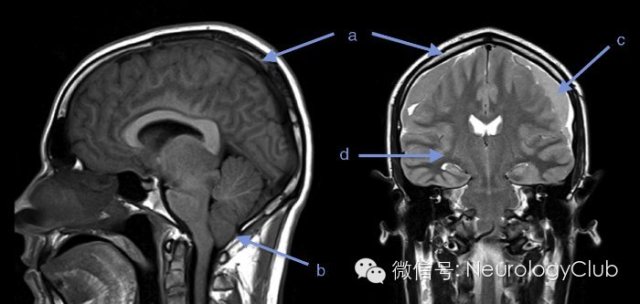

(a)弥漫硬脑膜强化;(b)小脑扁桃体疝;

(c)硬膜下积液; (d)弥漫脑水肿

(引自:Intracranial hypotension syndrome: A post dural puncture headache? Rev Colomb Anestesiol. 2013;41:57-60.)